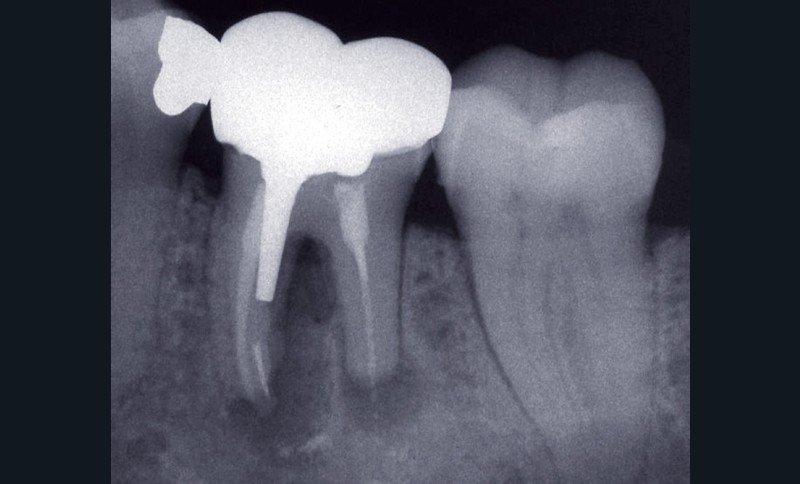

La PAC est fréquemment associée à un silence clinique, expliquant sa découverte généralement fortuite au cours d’une radiographie de contrôle (fig. 2).

Dans certains cas, une douleur à la percussion et éventuellement à la palpation des tissus mous peut être rencontrée. L’image radiographique associée est celle d’une lésion granulomateuse ou d’un kyste. En l’absence de traitement approprié ou d’une diminution des défenses de l’hôte, la lésion peut s’exacerber sous la forme d’un abcès phœnix. La dent devient douloureuse et sensible à la percussion, les tissus mous sont œdematiés et douloureux à la palpation. La présence d’une petite fistule peut parfois être objectivée cliniquement (fig. 3) [13].

La PAC peut perdurer durant de longues années et présenter des phases avec fistulisation durant lesquelles la dent ne présente généralement pas de symptomatologie. Une fermeture spontanée de l’ostium fistulaire entraîne parfois l’exacerbation aiguë sous la forme d’un abcès.